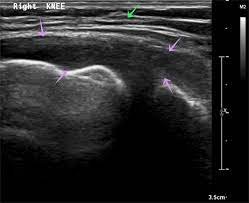

Ultrasound-Guided PRP Therapy

Ultrasound imaging utilizes high-frequency sound waves to create detailed images of soft tissues, including muscles, tendons, ligaments, and synovial structures within the knee joint.

• Visualization of Soft Tissues: Ultrasound of the knee joint Ultrasound guidance allows for the visualization of soft tissue structures within the knee, including the synovium, menisci, and ligaments, which may be difficult to assess using other imaging modalities.

• Precise Needle Placement: Ultrasound imaging provides real-time visualization of the needle as it enters the knee joint, enabling our practitioners to accurately guide the needle to the target site while avoiding adjacent structures.

• Assessment of Joint Pathology: Ultrasound can help identify areas of joint inflammation, synovial hypertrophy, and cartilage degeneration, providing valuable diagnostic information to guide treatment planning and PRP injection.